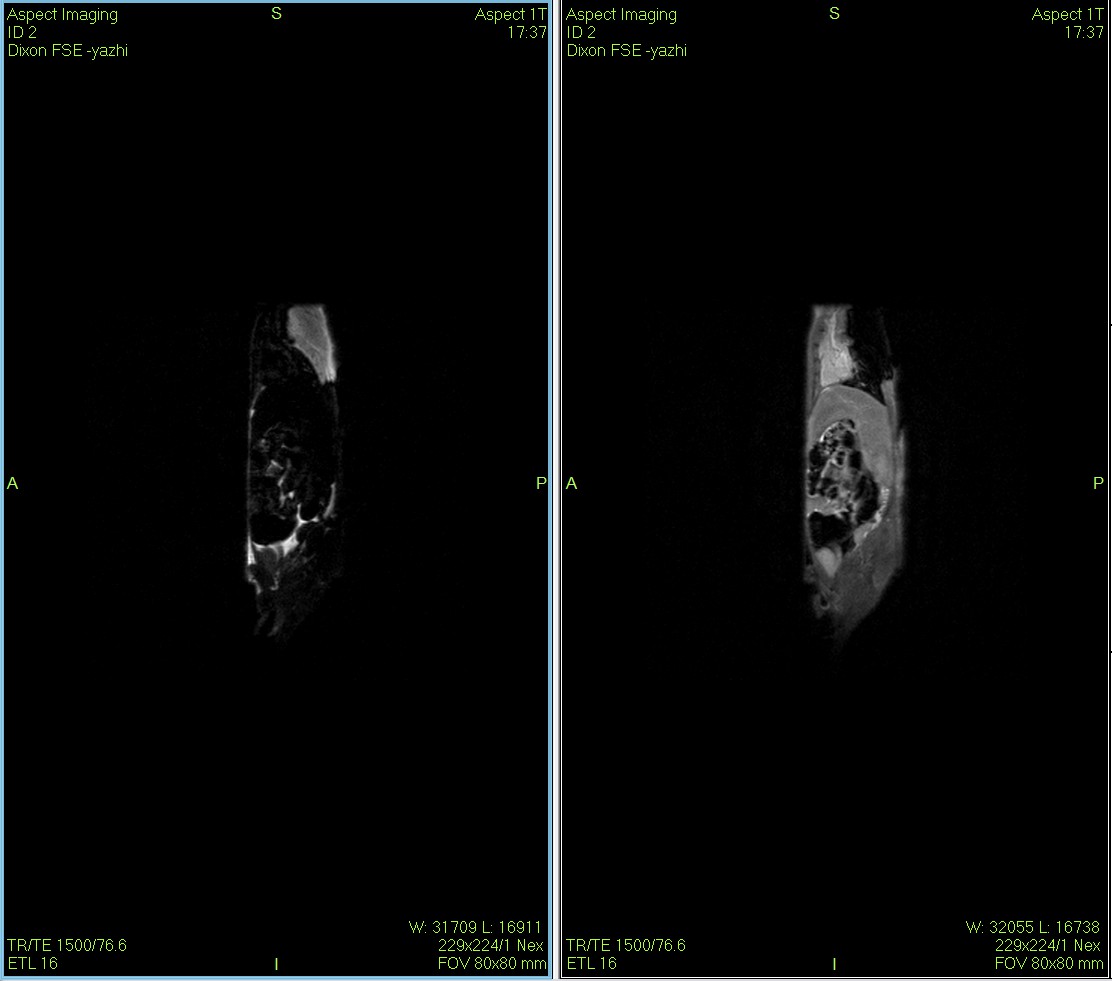

Dixon脂肪抑制技术是由Dixon 提出,其基本原理是利用水、脂肪的化学位移差异,使用不同的回波时问,分别采集水和脂肪质子的in Phase 和 opposed -phase两种回波信号。

使用仪器: 小动物核磁共振成像仪NM21-040H-I 小动物核磁共振成像仪NM20-060H-I 小动物核磁共振成像仪NM42-040H-I